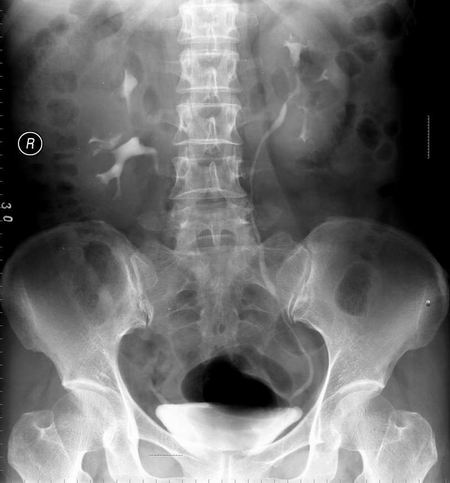

以下是引用向医生在2005-2-3 16:50:59的发言:[br]右侧肾盂上部及上肾盏受压,压迹呈弧形,边缘光滑,肾盏无侵蚀现象,局部肾轮廓似有增大。[br]意见:右肾上极占位。

以下是引用lkc8963在2005-2-9 20:43:32的发言:[br]支持右上极良性占位性病变.右肾区无钙化,局部无明显突出,肾盏受压变形,受压肾盏间似见片状造影剂充盈,功能正常,可能为囊肿或肾盏憩室,因为病变与收集系统相通.